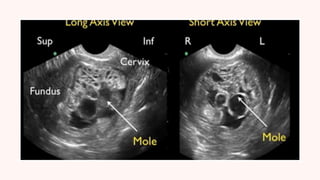

An ultrasound of your uterus often shows several

illed sacs instead of a placenta.

Ultrasound of complete mole shows :

no embryo or foetus, No amniotic

f

luid,A thick cystic placenta nearly

illing the

uterus,Ovarian cysts.

Ultrasound of partial molar pregnancy shows :

A foetus that’s smaller than expected,Low amniotic

luid,Placenta that appears unusual.